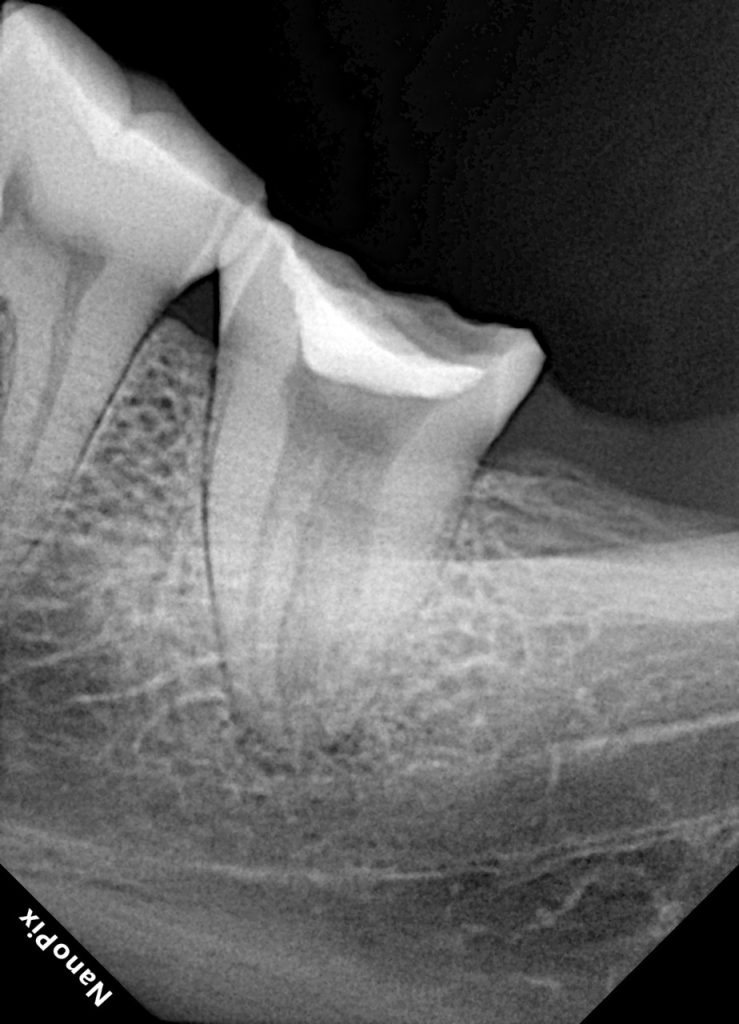

The patient presented with discomfort on biting and a history of intermittent dull pain on the upper left posterior side. Radiographic examination revealed previously untreated carious involvement extending into the pulp chamber of tooth #7.

- Fig 1. Pre-operative radiograph showing carious involvement.